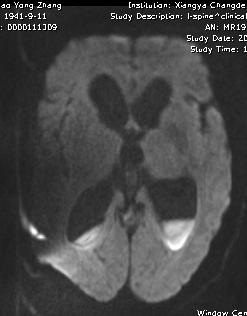

补充图片,DWI也证实T2、FLAIR上四脑室、侧脑室似有液平的地方,是积脓。

绿色无坑,充分体现一个临床病例的特点,急性起病,发烧,神经功能缺损。影像上脑室增大,T2、FLAIR上四脑室似有积脓,室管膜高信号。很多人都猜对了。